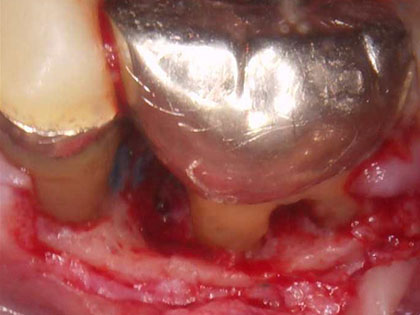

治療中の写真がこちら

術中の写真では細菌がたまっており取り除くと骨が溶けてなくなっていて空洞になっています